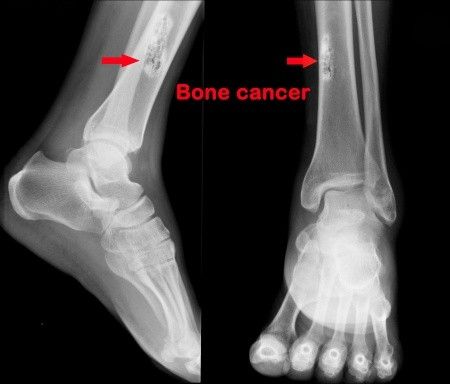

Bagaimana mendiagnosis kanker tulang?

Dokter akan melakukan wawancara medis mendetil dan pemeriksaan fisik menyeluruh, selain itu akan dilakukan juga pemeriksaan penunjang seperti bone scan, CT-scan, MRI, X-ray, ataubiopsi. Setelah diagnosis ditegakkan, barulah dokter akan menentukan stadium kanker. (Baca: 10 Cara Menghindari Kanker)